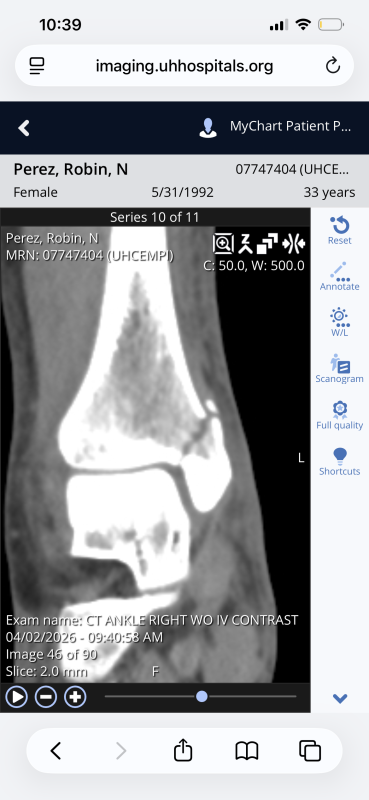

I broke my right ankle the night of 3/31. I am unable to work until further notice and my husband needs to stay home to assist me through the next couple of weeks. We have six children that we care for, two of whom aren‘t in school yet. I am also being recommended surgery on the break which will change my recovery time. We already don’t make much money to provide our needs but this situation makes it much more difficult and is putting a lot of stress on our family. We don’t have much family and non of them are able to help financially or with the kids and daily responsibilities. Any amount will help if you’re able and is greatly appreciated! Please! We have had so many obstacles these last few years and it’s been tough to continually face them alone.